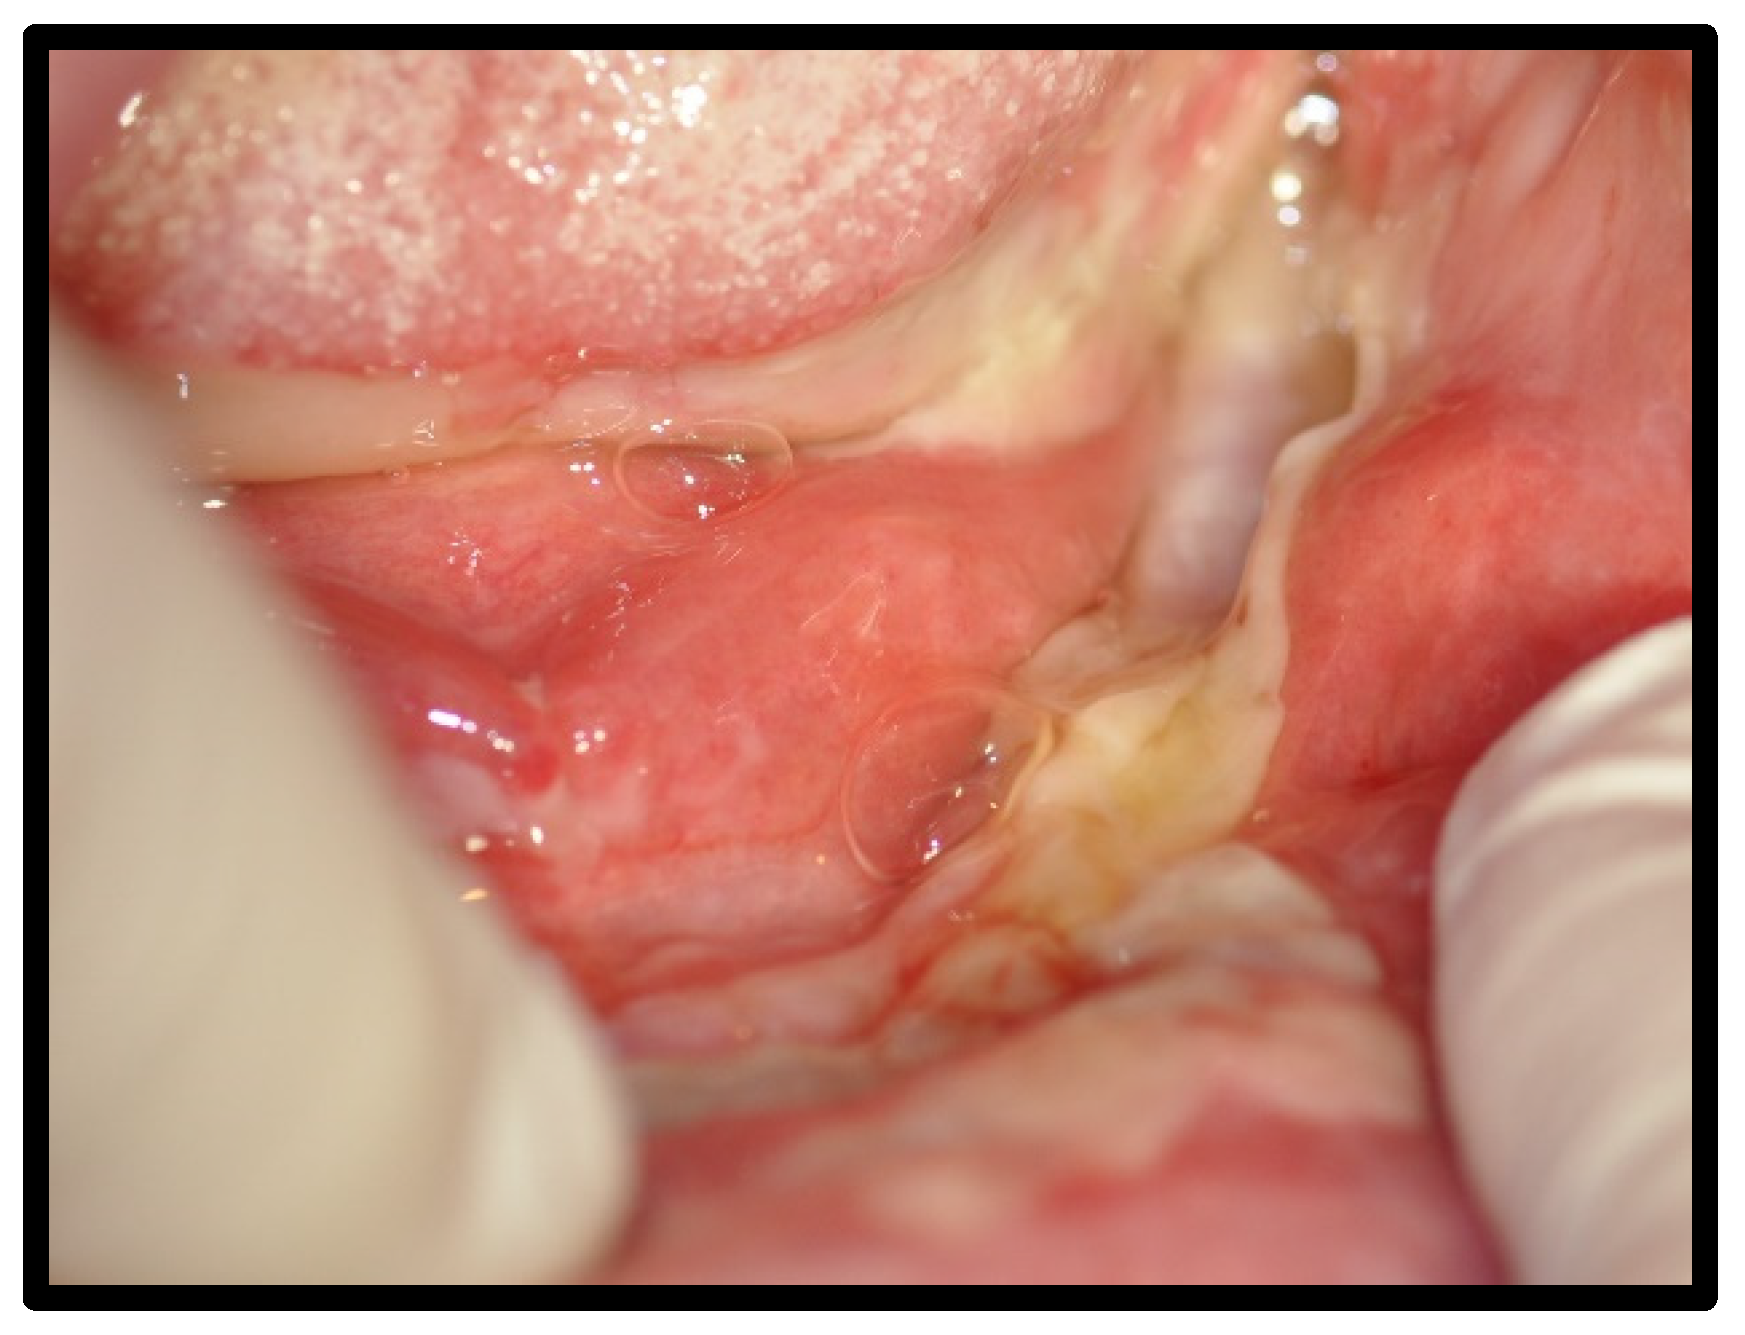

| Benign mucous membrane pemphigoid | 3 | 12.50 | |